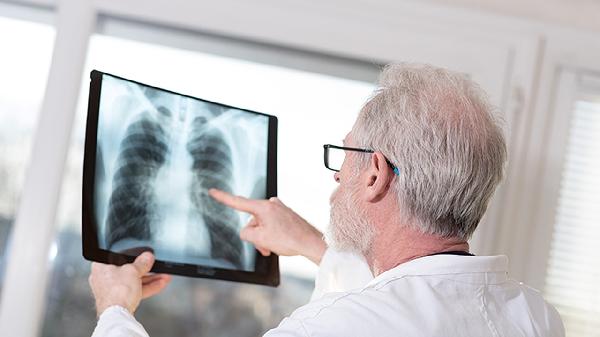

抗结核药物通常需要2-4周才能显著缓解症状。结核分枝杆菌生长缓慢,药物抑制细菌繁殖后,肺部炎症消退需要时间。服药初期可能出现持续低热、咳嗽、乏力等症状,属于治疗过程中的常见现象。部分患者对利福平、异烟肼等一线药物敏感度较低,导致症状改善延迟。痰涂片检查可帮助评估治疗效果,胸部影像学变化往往滞后于临床症状。